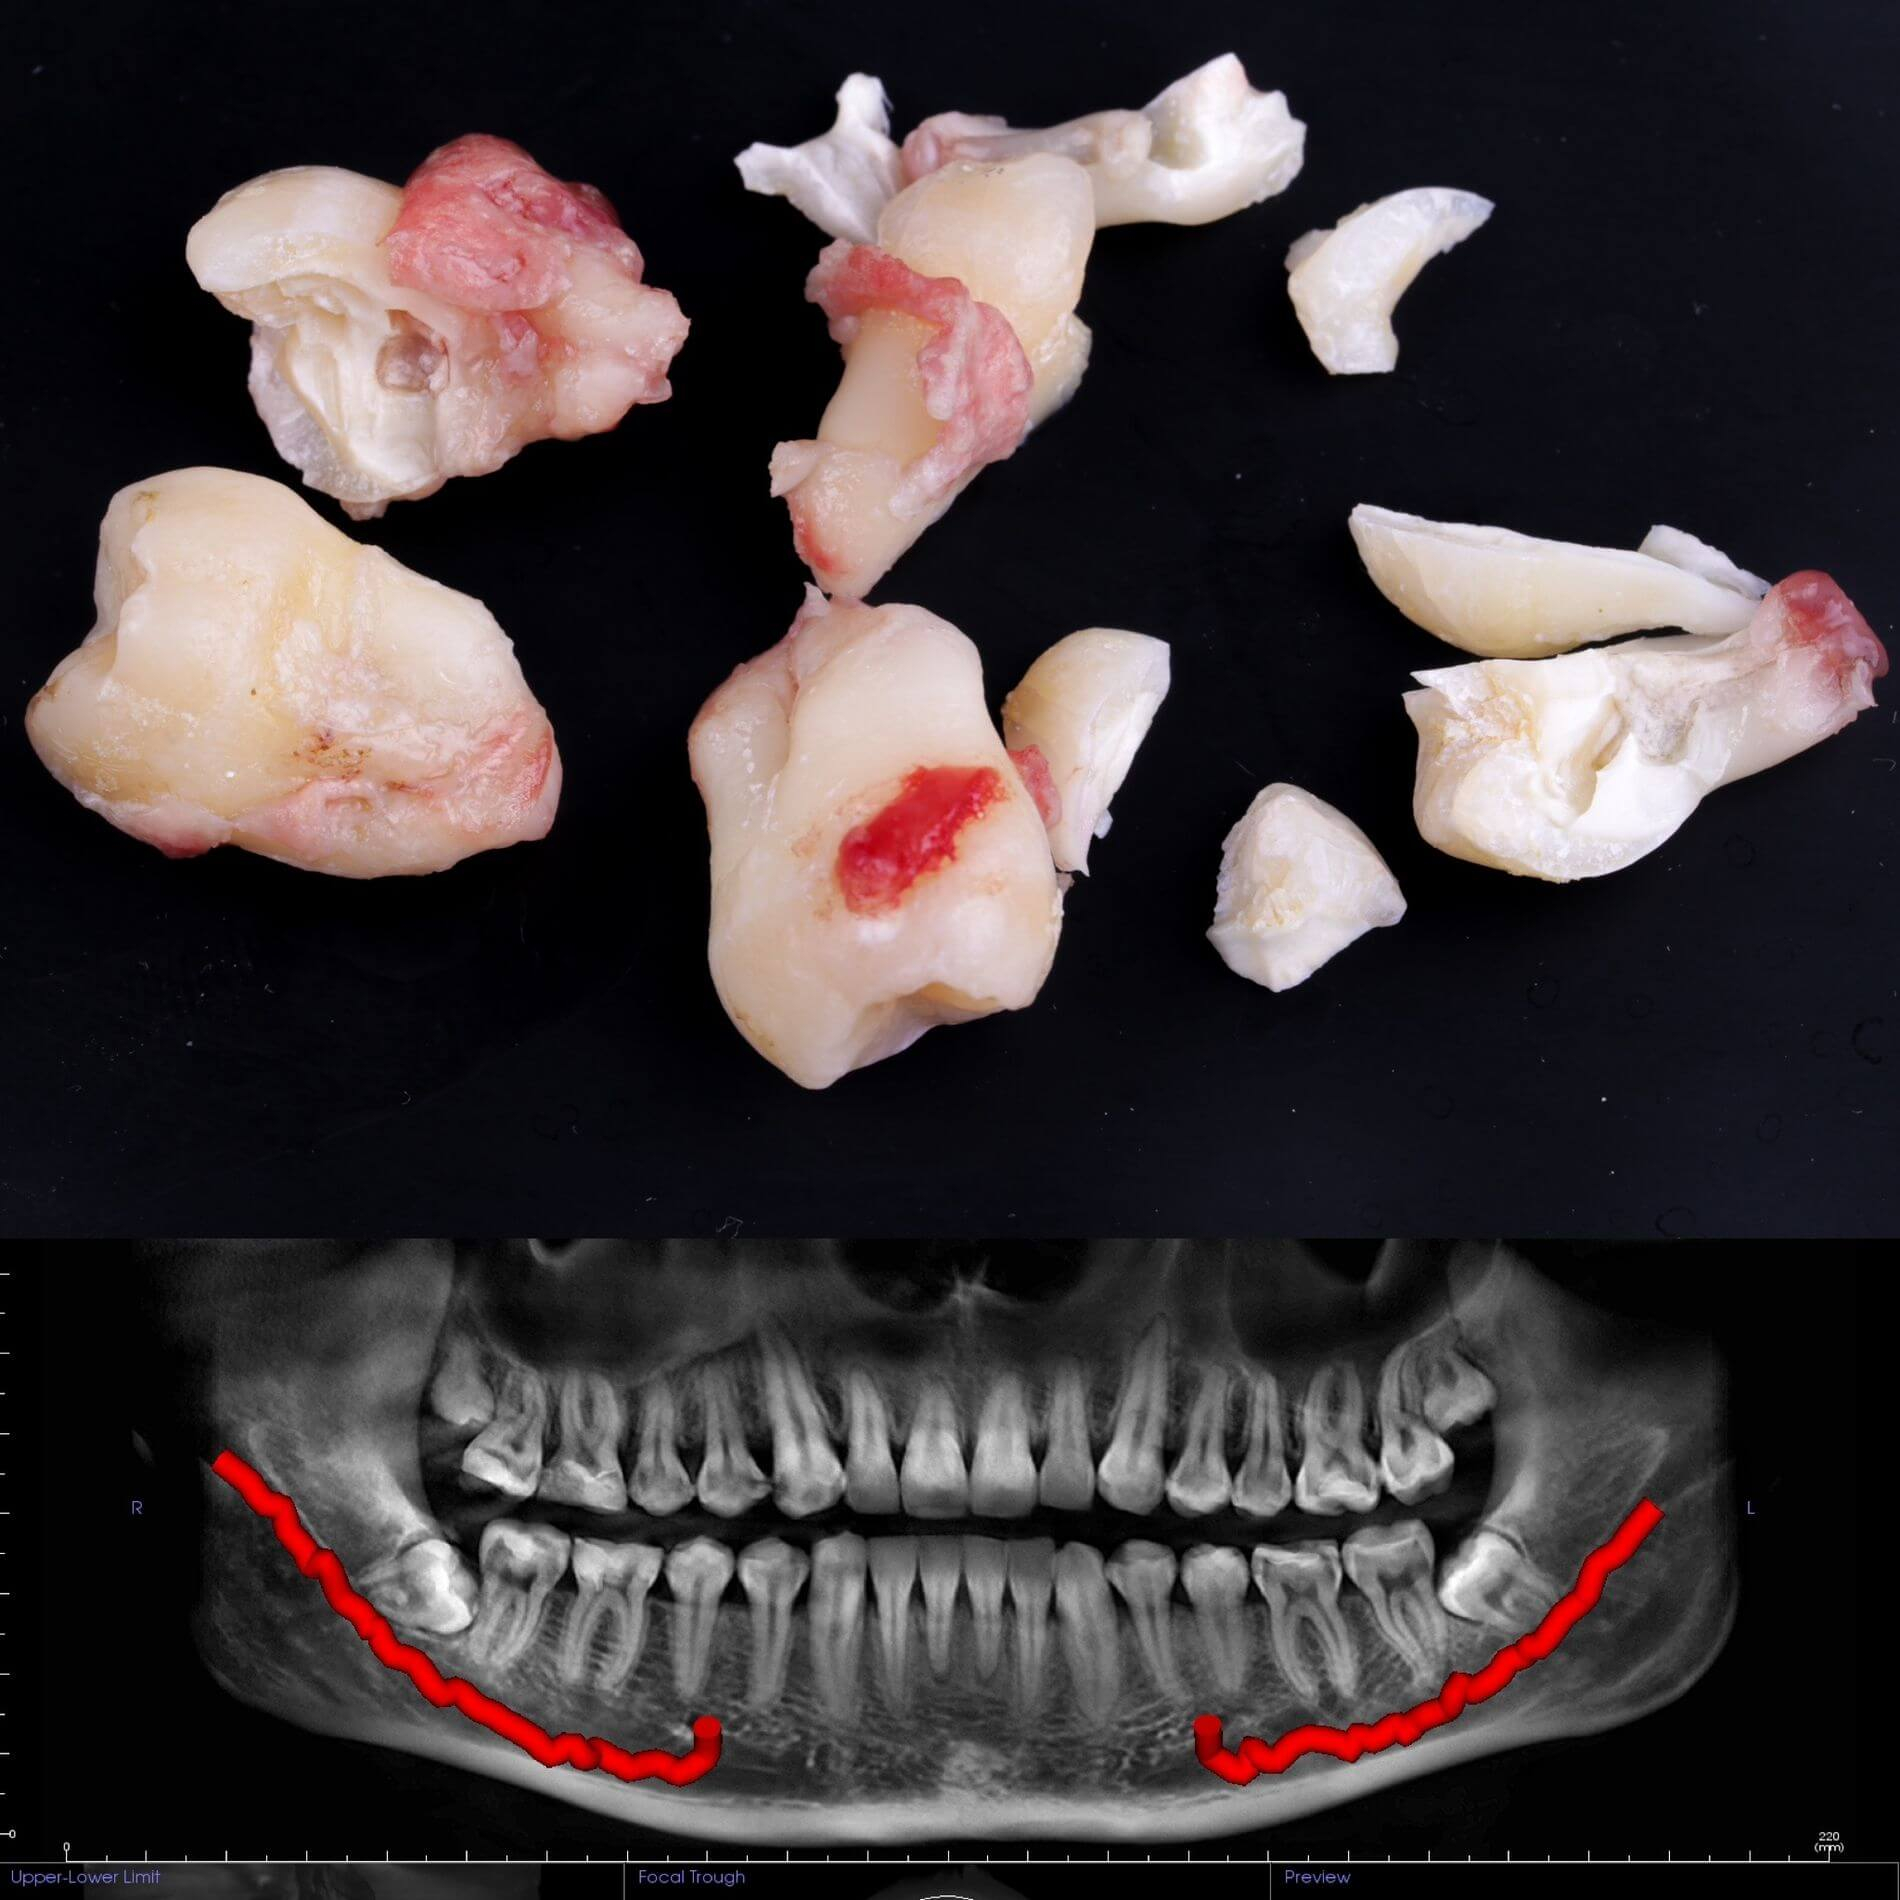

Виды удаления зубов мудрости

• Полное удаление зуба - если зуб полностью прорезался и имеет сросшиеся корни.

• Отдельное удаление коронки зуба и его корней - если зуб прорезан и корни растут по отдельности.

• Удаление зуба по схеме 1 или 2 с разрезом десен - если зуб прорезан частично.

• Разрез десен, освобождение зуба от близлежащей кости ультразвуком и удаление по схеме 1 или 2 - если зуб не прорезался, но беспокоит.

Вырвать зуб мудрости во Львове можно проще, чем тебе кажется, в Космической стоматологии Драганчука. Начни этот путь с простого шага - первичной встречи с хирургом-стоматологом. На консультации мы сделаем основное - направим тебя на 3D компьютерную томографию, чтобы учесть близость нижнечелюстного нерва (нижние 8-ки) и верхнечелюстной пазухи (верхние 8-ки) и составим план удаления зубов.

Галерея